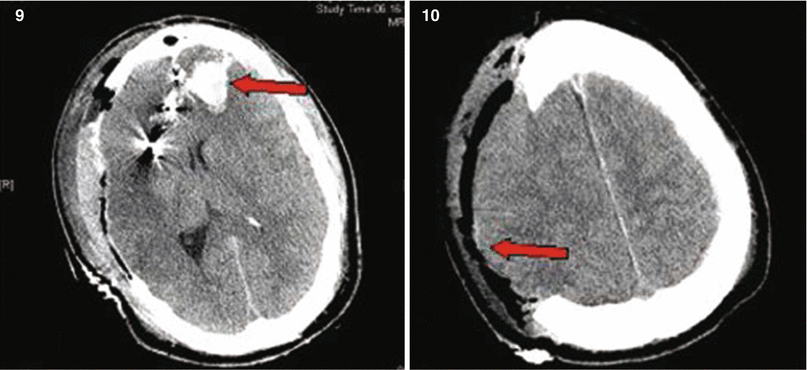

Fig. 27.4

Patient No. 4: a 26-year-old male, who sustained a solitary GSW to the head from distant range. Entry wound at the R ear canal, no exit wound. Plates 1 and 2: scout images A/P and lateral with evidence of multiple bullet fragments on the R extracranially and bilaterally intracranially. Note the large R-sided skull fracture. Arrows in panel 3 an 4 point at the bullet tract as seen on head CT with axial bone windows (3) and in matching coronal reconstructions (4). There are interspersed metal bullet fragments visible with their streak artifact. Arrow in plate 5 points at the temporal lobe hematoma. Arrow in plates 6 and 7 points at the hemicraniectomy site. Arrow in plate 8 points at the R MCA bifurcation with multpiple retained bullet fragments and a surgical clip for the traumatic avulsion site. Arrow in plate 9 indicates the allograft cranioplasty. And plate 10 shows a small left frontal inraparenchymal hematoma